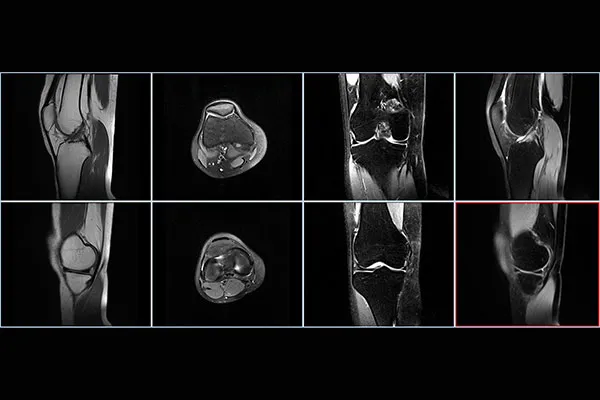

performs a thorough evaluation, including imaging studies like X-rays, CT scans, or MRIs, to confirm the presence and location of the osteoid osteoma and understand the osteoma cause.